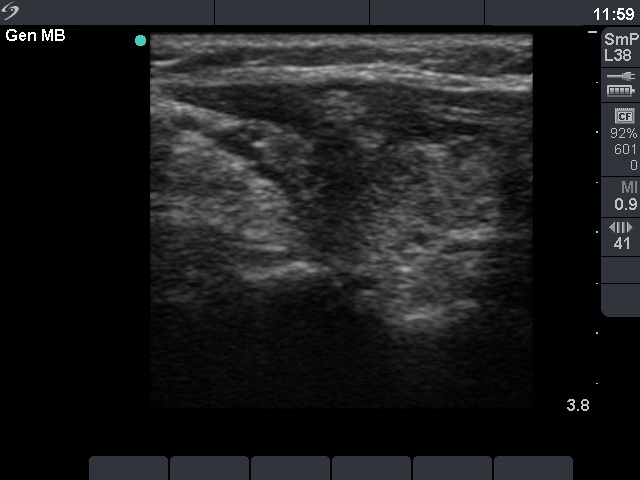

Granulation around surgical thread (cytological diagnosis) - case 981

The granulation pointed with calipers is located within the sternocleidomastoid muscle .